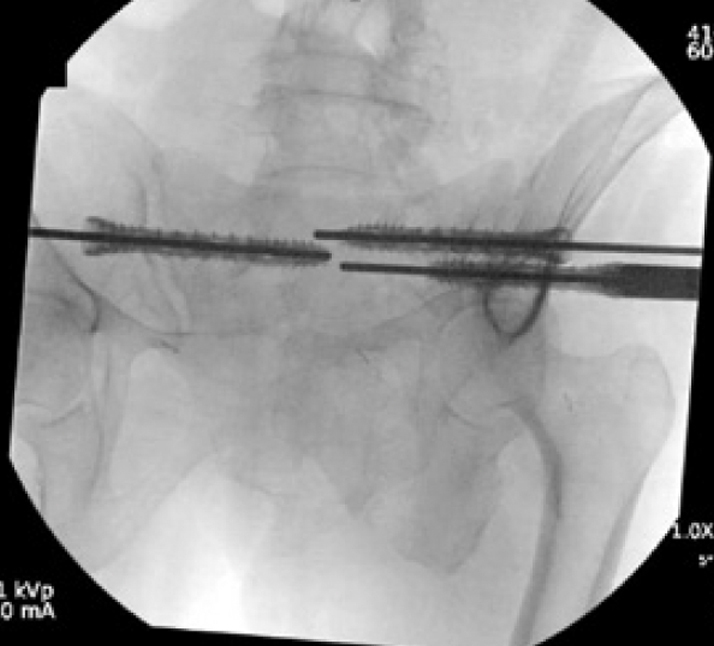

Surgical treatment:

• Bilateral sacral fracture fixation with iFuse TORQ®

Post-op:1,2

• Tolerated procedure well

• Immediate weight bearing as tolerated

• Ambulated 150 feet POD 1 and discharged home

• Pain improvement and healed fracture at 2 months

• No progression of kyphotic deformity